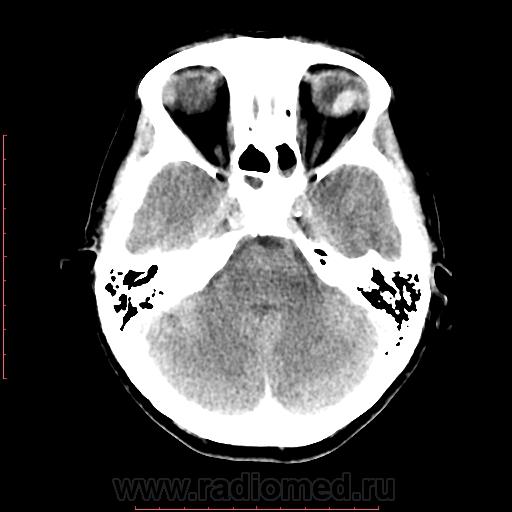

КТ орбит. Образование левого глазного яблока

Женщина 57 лет обратилась с жалобами на снижение зрения левого глаза. На УЗИ объемное образование левого глаза. Написал DDs меланома, ретинобластома.

Меланома - да, надо исключать. (наиболеее вероятно).

Рентинобластома - крайне маловероятна (после 5-ти лет эта опухоль практически не встречается).

Я тоже склоняюсь больше в сторону меланомы. Ретинобластома врожденная опухоль, в 90% случаев диагностируется как вы и сказали до 5 лет, у взрослых встречается редко и в 95% содержит обызвествления, но в дифф.ряд указал на всякий случай.